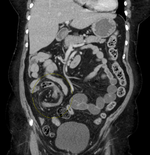

CT scan of a small bowel volvulus. It shows two juxtaposed segments of narrowing, which is the spot of mesentery rotation. The other signs indicate strangulation.